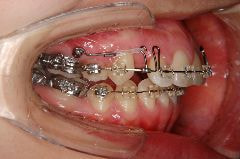

歯科矯正用アンカースクリューの使用例

例1)

➡︎